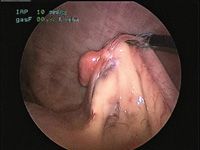

Photo 1: An intraoperative photo of laparoscopic graspers elevating the uterine horn and ovary.

Once the abdomen is appropriately insufflated, introduce the telescope through the first cannula, and place an instrument cannula half way between the subumbilical port and the pubis on midline. Through this port, use instruments to grasp the proper ligament and elevate the ovary (Photo 1). Then tack the ovary to the body wall by passing a suture percutaneously through the body wall and then back out through the skin. Grasp the free ends of the suture next to the body wall to keep the ovary suspended. Be careful not to pass this suture through the ovarian pedicle as hemorrhage will obscure visualization and may require conversion to an open procedure. Next, introduce a vessel-sealing device, and transect the proper ligament, pedicle and mesovarium (Photo 2).